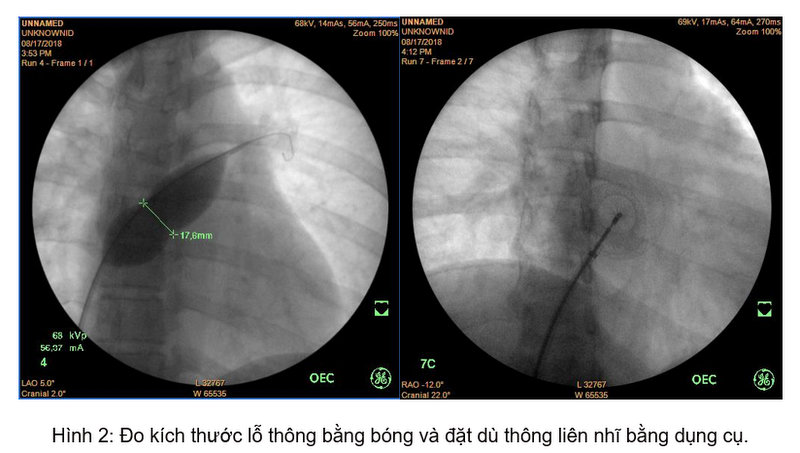

Xác định đây là nguyên nhân gây ra các triệu chứng trên bệnh nhân cũng như khảo sát kỹ cho thấy hình thái cấu trúc, chức năng tim phù hợp, bệnh nhân đã được chỉ định điều trị bằng phương pháp đóng lỗ thông liên nhĩ bằng dù Amplatzer ASD Occluder đường kính 18 mm qua da bằng dụng cụ dưới hướng dẫn của hệ thống tăng sáng số hóa xóa nền và siêu âm tim doppler màu.